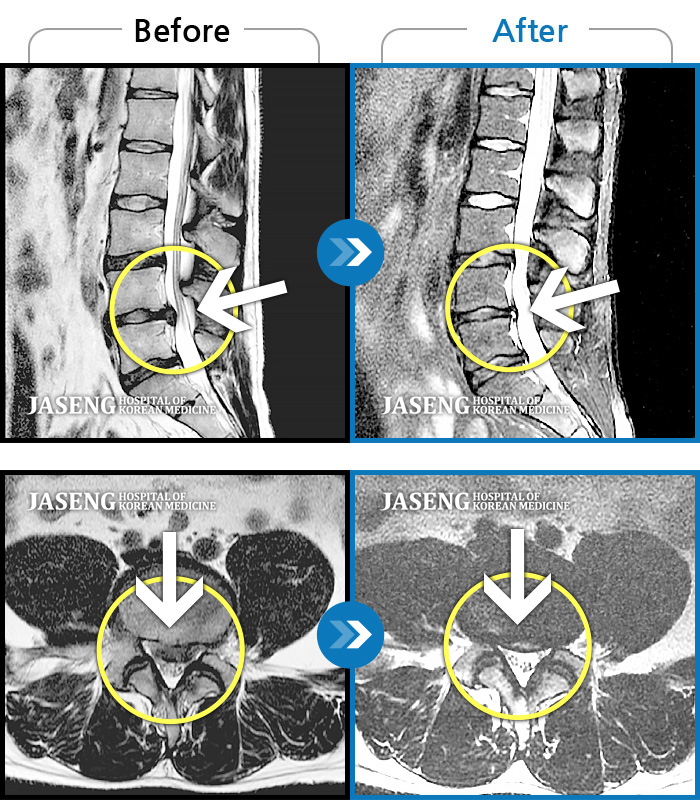

허리디스크

강남 · 강만호 원장

허리 통증 및 왼쪽 다리 근력저하 감각저하로 일상생활이 불가능했습니다.

촬영시기

2024.05.18 ~ 2025.12.03

2025.12.19

조회수 101